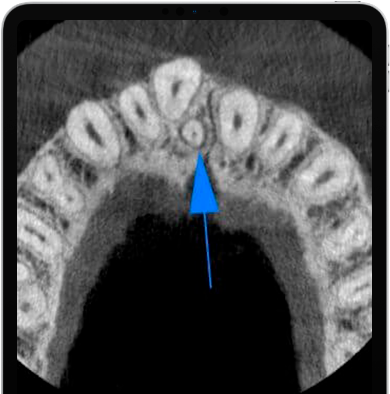

Ele fornece imagens detalhadas graças à sensibilidade do sensor CMOS recém-desenvolvido. GO 2D / 3D oferece diagnósticos rápidos e precisos com várias opções de software de aquisição de imagens projetadas para obter imagens 2D de alta qualidade para todas as necessidades de diagnóstico. Imagens panorâmicas excelentes, nítidas e detalhadas com tecnologia ApT (Tratamentos de imagem autoadaptativa). A função aPAN (Adaptive PAN) permite que cinco camadas de imagens panorâmicas sejam capturadas em uma única varredura para escolher a mais adequada para o escopo do exame.

Compacta e disponível com sensor PAN-CEPH relocável, a extensão CEPH é equipada com uma unidade de suporte de cabeça dedicada com dois comprimentos de haste lateral disponíveis. O aplicativo CEPH pode ser integrado no momento da compra, mas também adaptado em equipamentos fornecidos na versão CEPH Ready. Todos os exames são realizados de acordo com protocolos dedicados para adultos e crianças, otimizados para reduzir a exposição do paciente com base nos requisitos reais de digitalização. Avaliações precisas antes da aplicação de aparelho dentário, articulação temporomandibular (ATM) e imagem do seio maxilar, telerradiografias lateral e frontal.